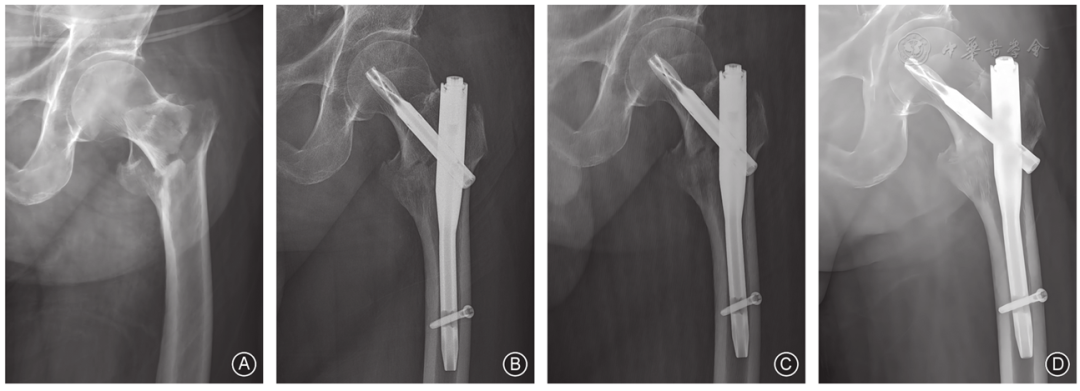

图2 男,75岁,左侧股骨转子间骨折,接受PFNA内固定治疗 A 术前髋关节正位X线片示股骨转子间骨折移位 B 术后1周髋关节正位X线片示内固定位置良好 C 术后3个月髋关节正位X线片示骨折线模糊 D 术后9个月髋关节正位X线片示骨折愈合